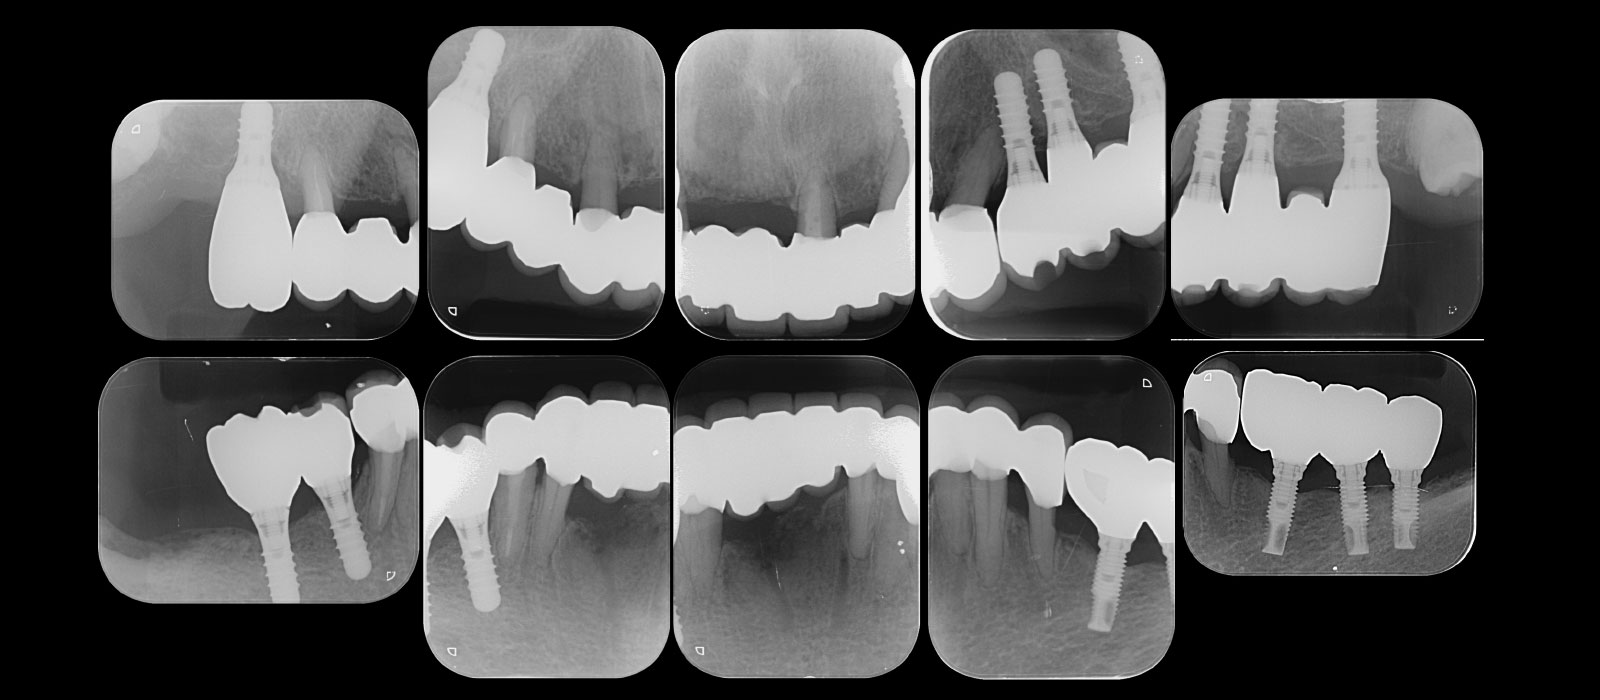

2.治療前の検査

歯周病の状態をレントゲンとポケット検査で調べて、治療方針を提案しました。

治療後のレントゲン写真です。

治療終了から7年経過していますが、定期健診にも来られていて、良い状態が続いています。